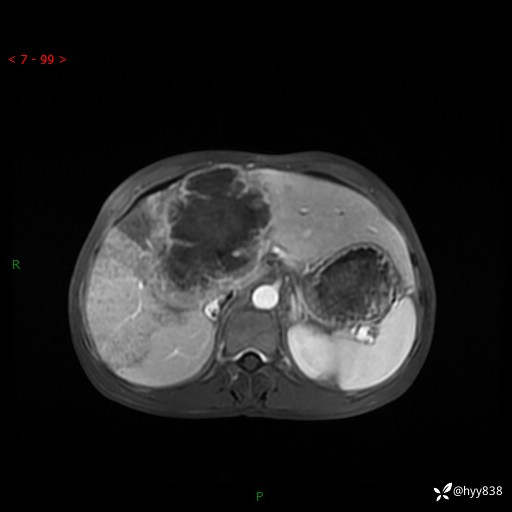

【患者信息】:58岁/男

【主诉】:发现肝占位2天

【现病史及既往史】:患者2天前于当地市第五医院查上腹部磁共振提示:肝脏S4段占位性病变,肝ca可能,胆囊结石,腹膜后多发肿大淋巴结,无剑突下及右上腹疼痛不适,无明显反酸、嗳气,无畏寒、头晕、头痛,无尿频、尿急、尿痛等不适,今为求进一步治疗特来我院就诊,门诊以“肝占位”收住我科。 患者病程中精神、睡眠、饮食尚可,大小便正常、体力体重无明显变化

【检查】:肝脏MRI】平扫+增强